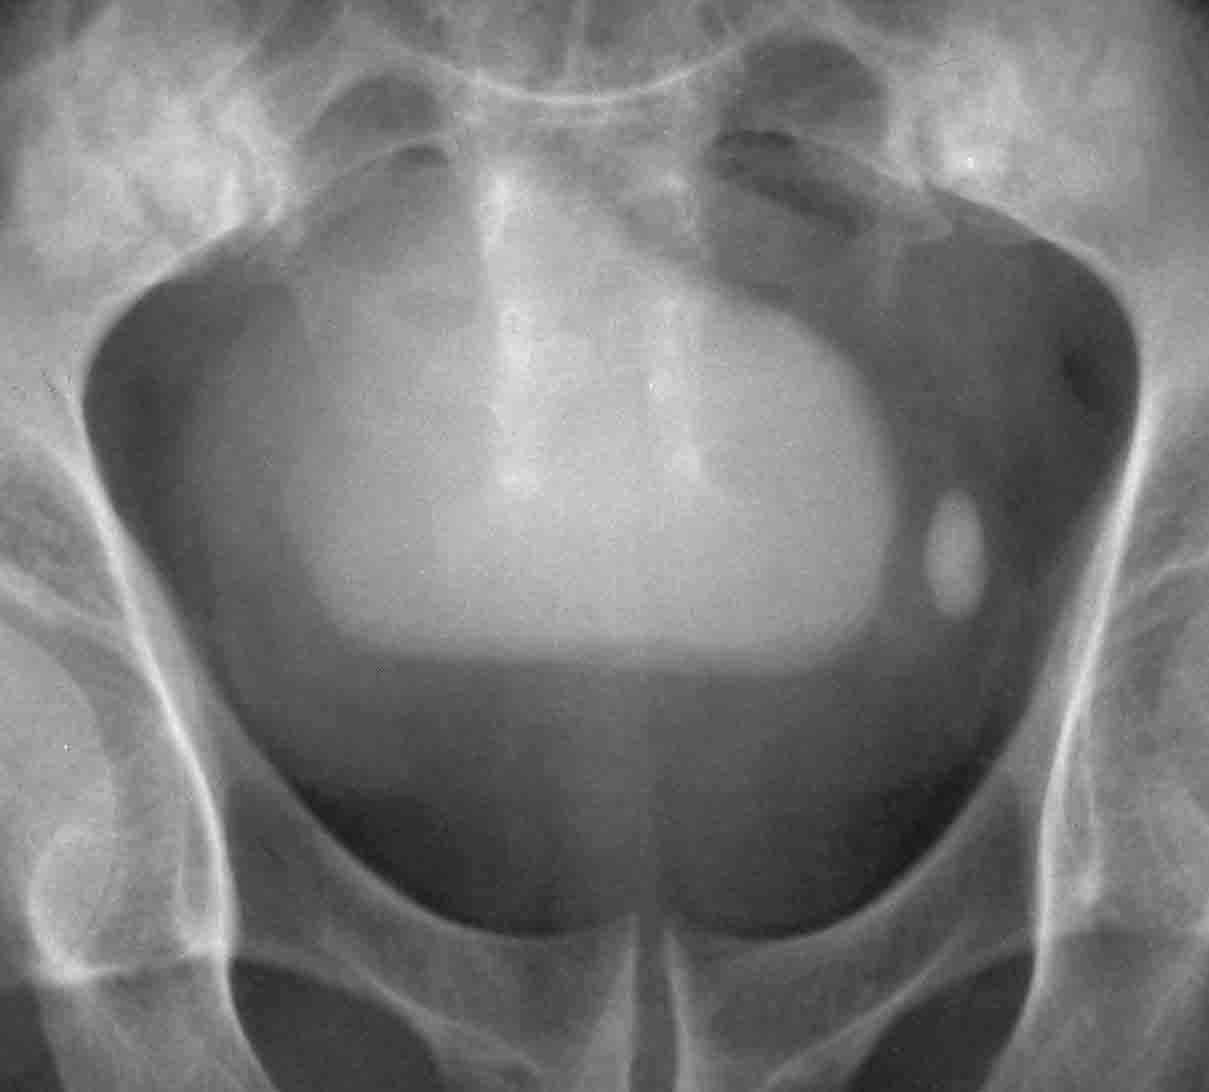

性别:男 60岁,因左侧输尿管末端结石行ivp,上述5张片分别为kub片和7分 15分 30分及120分钟延迟片.

随着时间的延长,膀胱内高密度病灶密度逐渐增高,支持膀胱炎并膀胱巨大憩室的诊断.

1、左侧输尿管下段结石。2、膀胱炎并膀胱巨大憩室。

1、左侧输尿管下段结石。2、膀胱炎并膀胱巨大憩室可能

输尿管下段结石,膀胱内高密度考虑巨大憩室可能